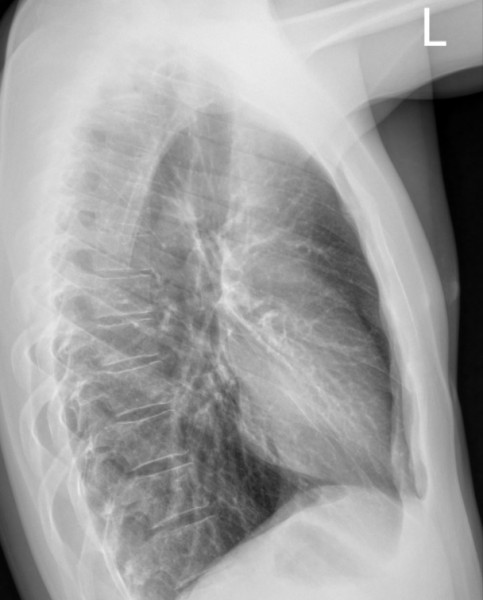

Wczoraj spadłem z ok dwóch metrów lewym bokiem na metalowe belki. Cały impet uderzenia przyjęła klatka piersiowa. Na chwilę straciłem oddech, ale potem wszystko wróciło do normy, pozostał tylko ból żeber. Dzisiaj ból się nasilił i poszedłem do lekarza no i zrobiono mi zdjęcie RTG. Niestety na konsultację z chirurgiem muszę dosyć długo czekać...a ból jest podczas zwykłych czynności i nasila się podczas głębokiego oddychania, kaszlu, "pociągania" nosem...ogólnie ból sprawia wszystko co powoduje "ruch" żeber.

Dotykowi żeber po lewej stronie również towarzyszy ból. Leżeć na obolałym boku jak i na plecach nie mogę bo ból temu towarzyszący jest nie do wytrzymania,

Czy mógłbym prosić o ocenę zdjęcia czy udać się z tym na SOR czy czekać posłusznie na wizytę u dr chirurga?

zdj2.jpg

Zdj1.jpg